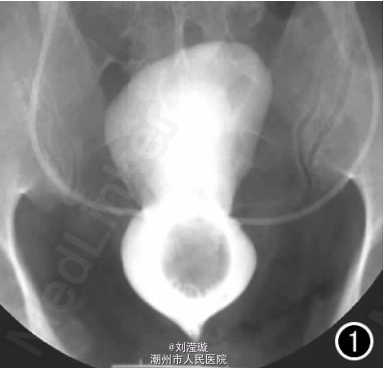

腹部B超示双肾增大,双肾慢性肾病声像;双肾中度积液伴双输尿管上段扩张。 IVPshi双侧输尿管中或下段梗阻。 膀胱造影:经尿道置管后,注射对比剂充盈膀胱,膀胱下半部先充盈,继续灌注对比剂后见膀胱完全显影,膀胱形态异常,呈“倒葫芦状”(图1)。 CT增强扫描行延迟期 MPR重组,见双侧肾盂、肾盏扩张积液;双侧输尿管纡曲、扩张,下端呈鸟嘴样变窄;膀胱变形、体积减小(图2); MRI平扫示双侧肾盂、肾盏扩张积液,双侧输尿管扩张并下端鸟嘴样变窄,盆腔内多量脂肪沉积,分布于膀胱、直肠周围,T1WI、T2WI呈明显高信号,T2WI抑脂像呈稍高信号,膀胱受压变形、体积减小(图3a~c); MRU示双侧肾盂肾盏扩张、积液,双侧输尿管显著纡曲、扩张,下端鸟嘴样变窄,管壁光整,膀胱变形、体积较小、位置抬高(图3d)。